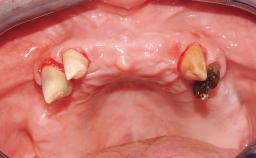

A 68-year-old, completely edentulous male patient presented for evaluation and treatment options. He reported excellent general health and was taking no regular medication. He had been edentulous for approximately 12 years, having lost his teeth to periodontal disease and dental caries. The patient’s chief complaint was incompetent function. His secondary concerns included his appearance and the desire for a predictable outcome. He attributed his reduced functional capacity to his lower complete denture, which he described as poor. He was particularly concerned with the denture’s instability and poor fit. In general terms, he was satisfied with the maxillary complete prosthesis. The maxillary prosthesis was characterized by adequate retention, stability, and support, although the fit was considered less than ideal.

Case Type Edentulous Mandible

Jaw Mandible

Area Full-Arch

# of Teeth All

# of Implants 6